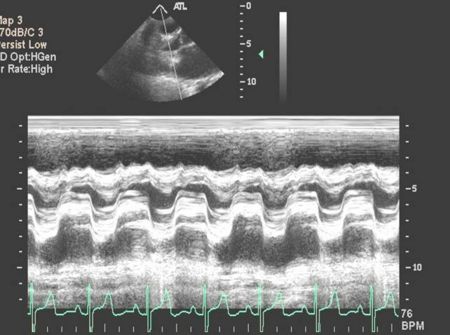

Aortic Valve M-mode Analysis

- During systole do the aortic valve leaflets oppose the aorta?

- Are the leaflets thick and calcified (bright)?

- Possible to have normal appearance on m-mode if non-calcific

- Are leaflets open throughout systole - HOCM, low-output state